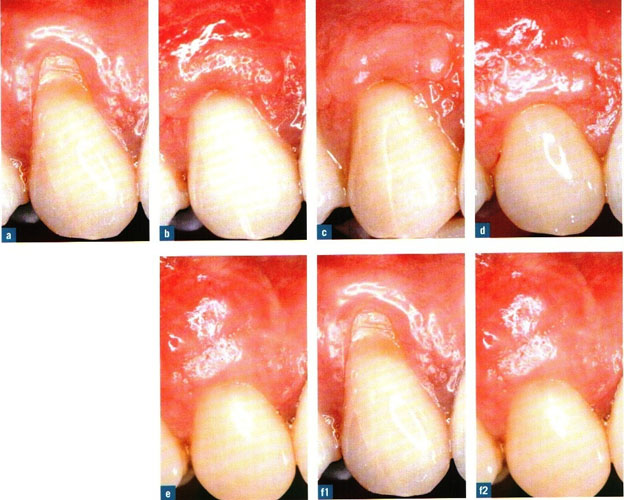

rejeneratif periodontoloji ameliyatı

Ayrıca genel ve lokal dişeti abseleri oluşabilir. Bu sorunun tedavisinde dişetinin açılarak dişik kök yüzeyinin temizlenmesi, civardaki iltihaplı dokunun (granülanyon dokusu) temizlenmesi ve kliniğimizde uyguladığımız yöntemle, o boşluklara yapay kemik + minematriks proteini (Emdogain (R) ) uygulaması yapılarak 6-8 ay sonra operasyon bölgelerinde yeniden alveol kemiği oluşumu sağlanmakta ve bu yolla belkide çekilecek bir diş ağızda tutulmaktadır.

1) Dişeti cebinde azalma 2) Dişeti iltihaplarının ortadan kalkması 3) Ataşman (dişetinin yeniden dişe yapışması) kazancı da operasyonun başarısının kanıtı olarak ortaya çıkar.